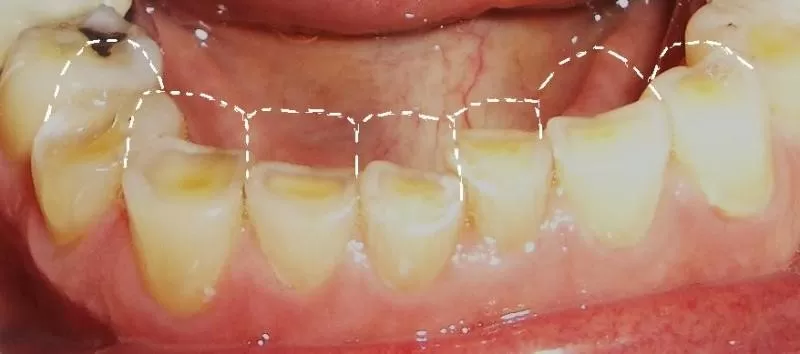

– Các răng bị mòn và ê buốt, thậm chí nứt, gãy.

Điều trị chỉnh nha hoặc điều chỉnh các răng gây cộm khớp, thay các răng giả mới để giúp bạn có được khớp cắn tốt. Đối với các trường hợp mòn răng nhiều gây sụp khớp, cần làm phục hồi toàn hàm (bằng mão sứ) để tái tạo lại kích thước dọc.